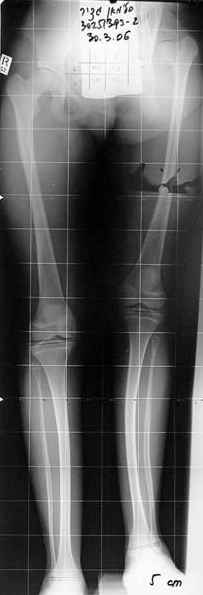

Слайд 1

Слайд 2

Слайд 3

Слайд 4

Devushka predstavlennaya na snimke nachala s LLD 9 cm, valgus deformation of the tibia, huge Trendelenburg( vidno na snimke).

Seichas : no LLD ,no Trendelenburg, reasonable hip motion.A samoe glavnoe ei ne predstoit kaghdye 10-15 let delat revision THR.

Пациент из сельской местности, школьник, ожирение 2-3 ст. Четкого мнения по поводу дальнейшего лечения у него и родителей нет, но надеются на возможность ходьбы. В течение всего периода с момента травмы ногу не нагружал. В настоящее время передвигается с одним костылем с компенсацией укорочения в обуви. Нейропатия седалищного нерва сохраняется на одном уровне (в основном за счет малоберцового н.). Активное сгибание колена 180-110, поднимает прямую ногу. Болей в тазобедренном суставе нет.